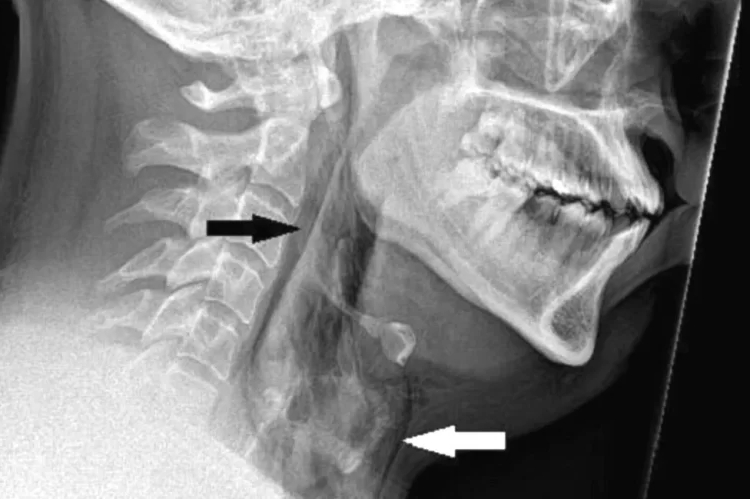

Однако в данном конкретном случае у неназванного пациента образовался разрыв трахеи диаметром 2 мм, что вызвало мучительную боль. Разрыв горла, известный в медицине как «спонтанная перфорация трахеи», представляет собой редкую и потенциально опасную для жизни травму, которая раньше не была связана с удушающим чиханием.

Когда мужчина прибыл в отделение неотложной помощи, он испытывал сильную боль, шея опухла с обеих сторон и он едва мог пошевелить головой. Он рассказал врачам, что за рулем у него случился приступ сенной лихорадки, и когда у него появилось побуждение чихнуть, он просто сдержал его, ущипнув нос и закрыл рот. В итоге у него было порвано горло.